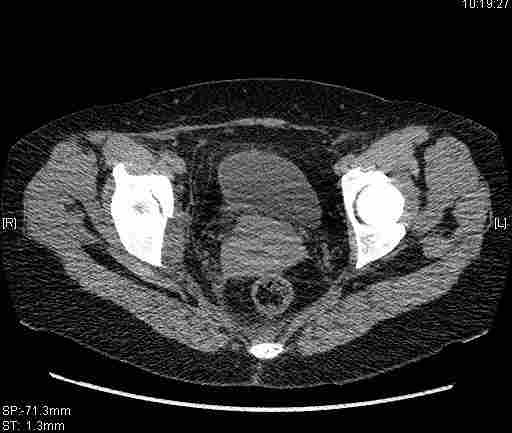

Удалось сегодня вывести пациентку в соседнюю больницу, где есть кт. Срезы сделаны только горизонтальные.

Следом 3d

Приветствую,Антон.Рункова рядом нет,но после полученных данных КТ,обсуждали совместно.Итог обсуждения-развернутый ответ дать не получится,т.к.срезы выбраны не информативные.Если ориентироваться на данные 3D,то ,ИМХО,можно лечить на вытяжении.